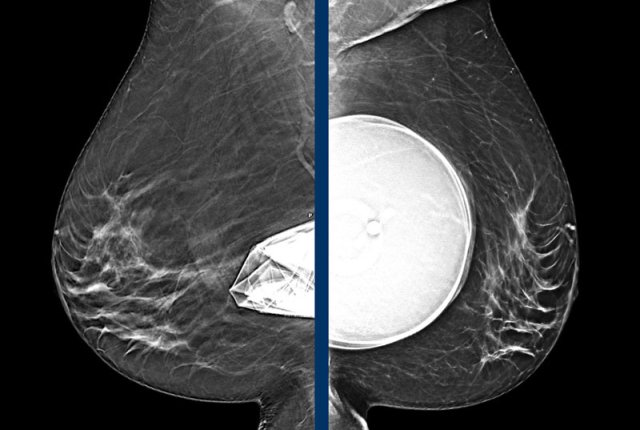

Mammography

Same patient before and after prepectoral breast augmentation.

Especially prepectoral implants can reduce mammographic assessment.

Still

mammography and 3D tomosynthesis can be well performed and in fact has the highest

PPV for recognition of extra capsular silicone.

It also objectively detects changes

in time, shows calcifications, can show surrounding fluid shadow and of course adds

important findings in fibroglandular tissue.